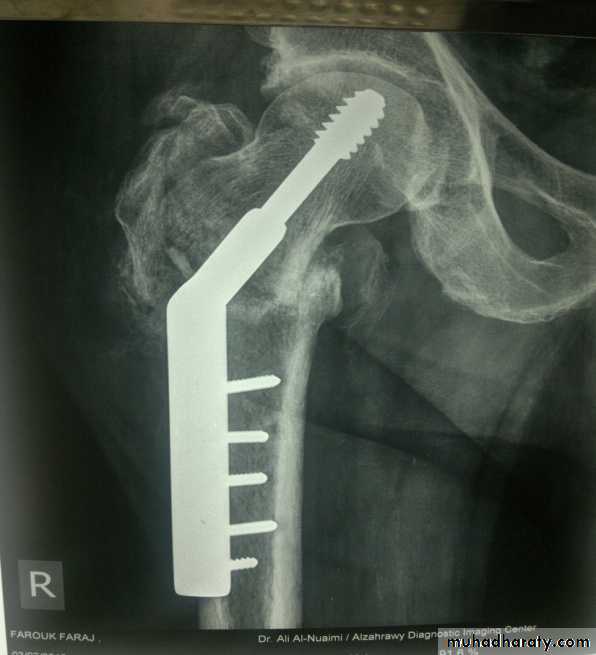

Intertrochanteric fractures are almost always treated by early internal fixation because :(a) to obtain the best possible position And

(b) to get the patient up and walking as soon as possible and thereby reduce the complications associated with prolonged recumbency.

The fracture is fixed with an angled device – preferably a sliding screw in conjunction with a plate (dynamic hip screw) or

intramedullary nail. or

95 degree screw-plate (L-Plate)

Dynamic hip screw

L-plate (fixed angle plate)